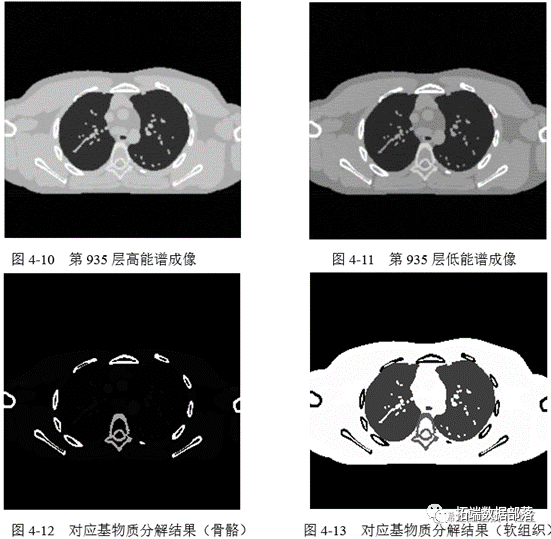

基于本章中所介绍的能谱 CT 重建理论,本项目选用人体组织中的骨骼和软组 织作为物质分解的两种基物质,利用 MATLAB 实现其具体算法。根据本章中对于基物质分解模型理论的详细介绍和各个公式,结合试验所得人体骨骼和软组织 的线性衰减系数,只需很短的代码就可以实现物质分解模型的仿真。本节试验目的是为 U-net 物质分解模型提供训练集和测试集。具体为利用 MATLAB 仿真出 基物质分解模型,将原始的能谱 CT 成像结果分解为骨骼和软组织,作为对应影像的标签。利用所得到的高、低能谱成像数据作为输入。

实验一采用高、低能谱图像作为输入数据,以软组织分割图像作为标签,训练 U-net 网络。网络训练结果如下